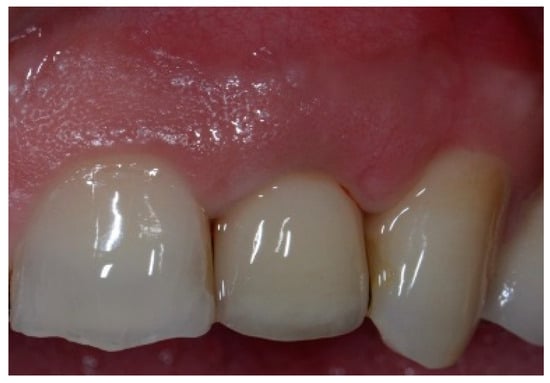

A 51-year-old male patient in good health and a non-smoker presented with a fractured maxillary canine with recurrent subgingival caries, and a failing root canal on the maxillary first premolar (Figure 18). The treatment plan consisted of the extraction of both teeth #11 and #12 roots, followed by the placement of implants. The preoperative surgical protocol described in patient 1 was followed. Figure 19 represents the residual boney defect associated with this area after implant placement. Similar to the previous cases, graft material was placed, and the area was closed for healing. Chairside temporary crowns were fabricated, followed by the placement of zirconia crowns in six months. Figure 20 represents the area three years after treatment.

Figure 18.

Clinical view of fractured tooth #11 and existing crown on tooth #12.

Figure 19.

Clinical view of implants and boney defects.

Figure 20.

Clinical view of final implant-supported ceramic crowns.